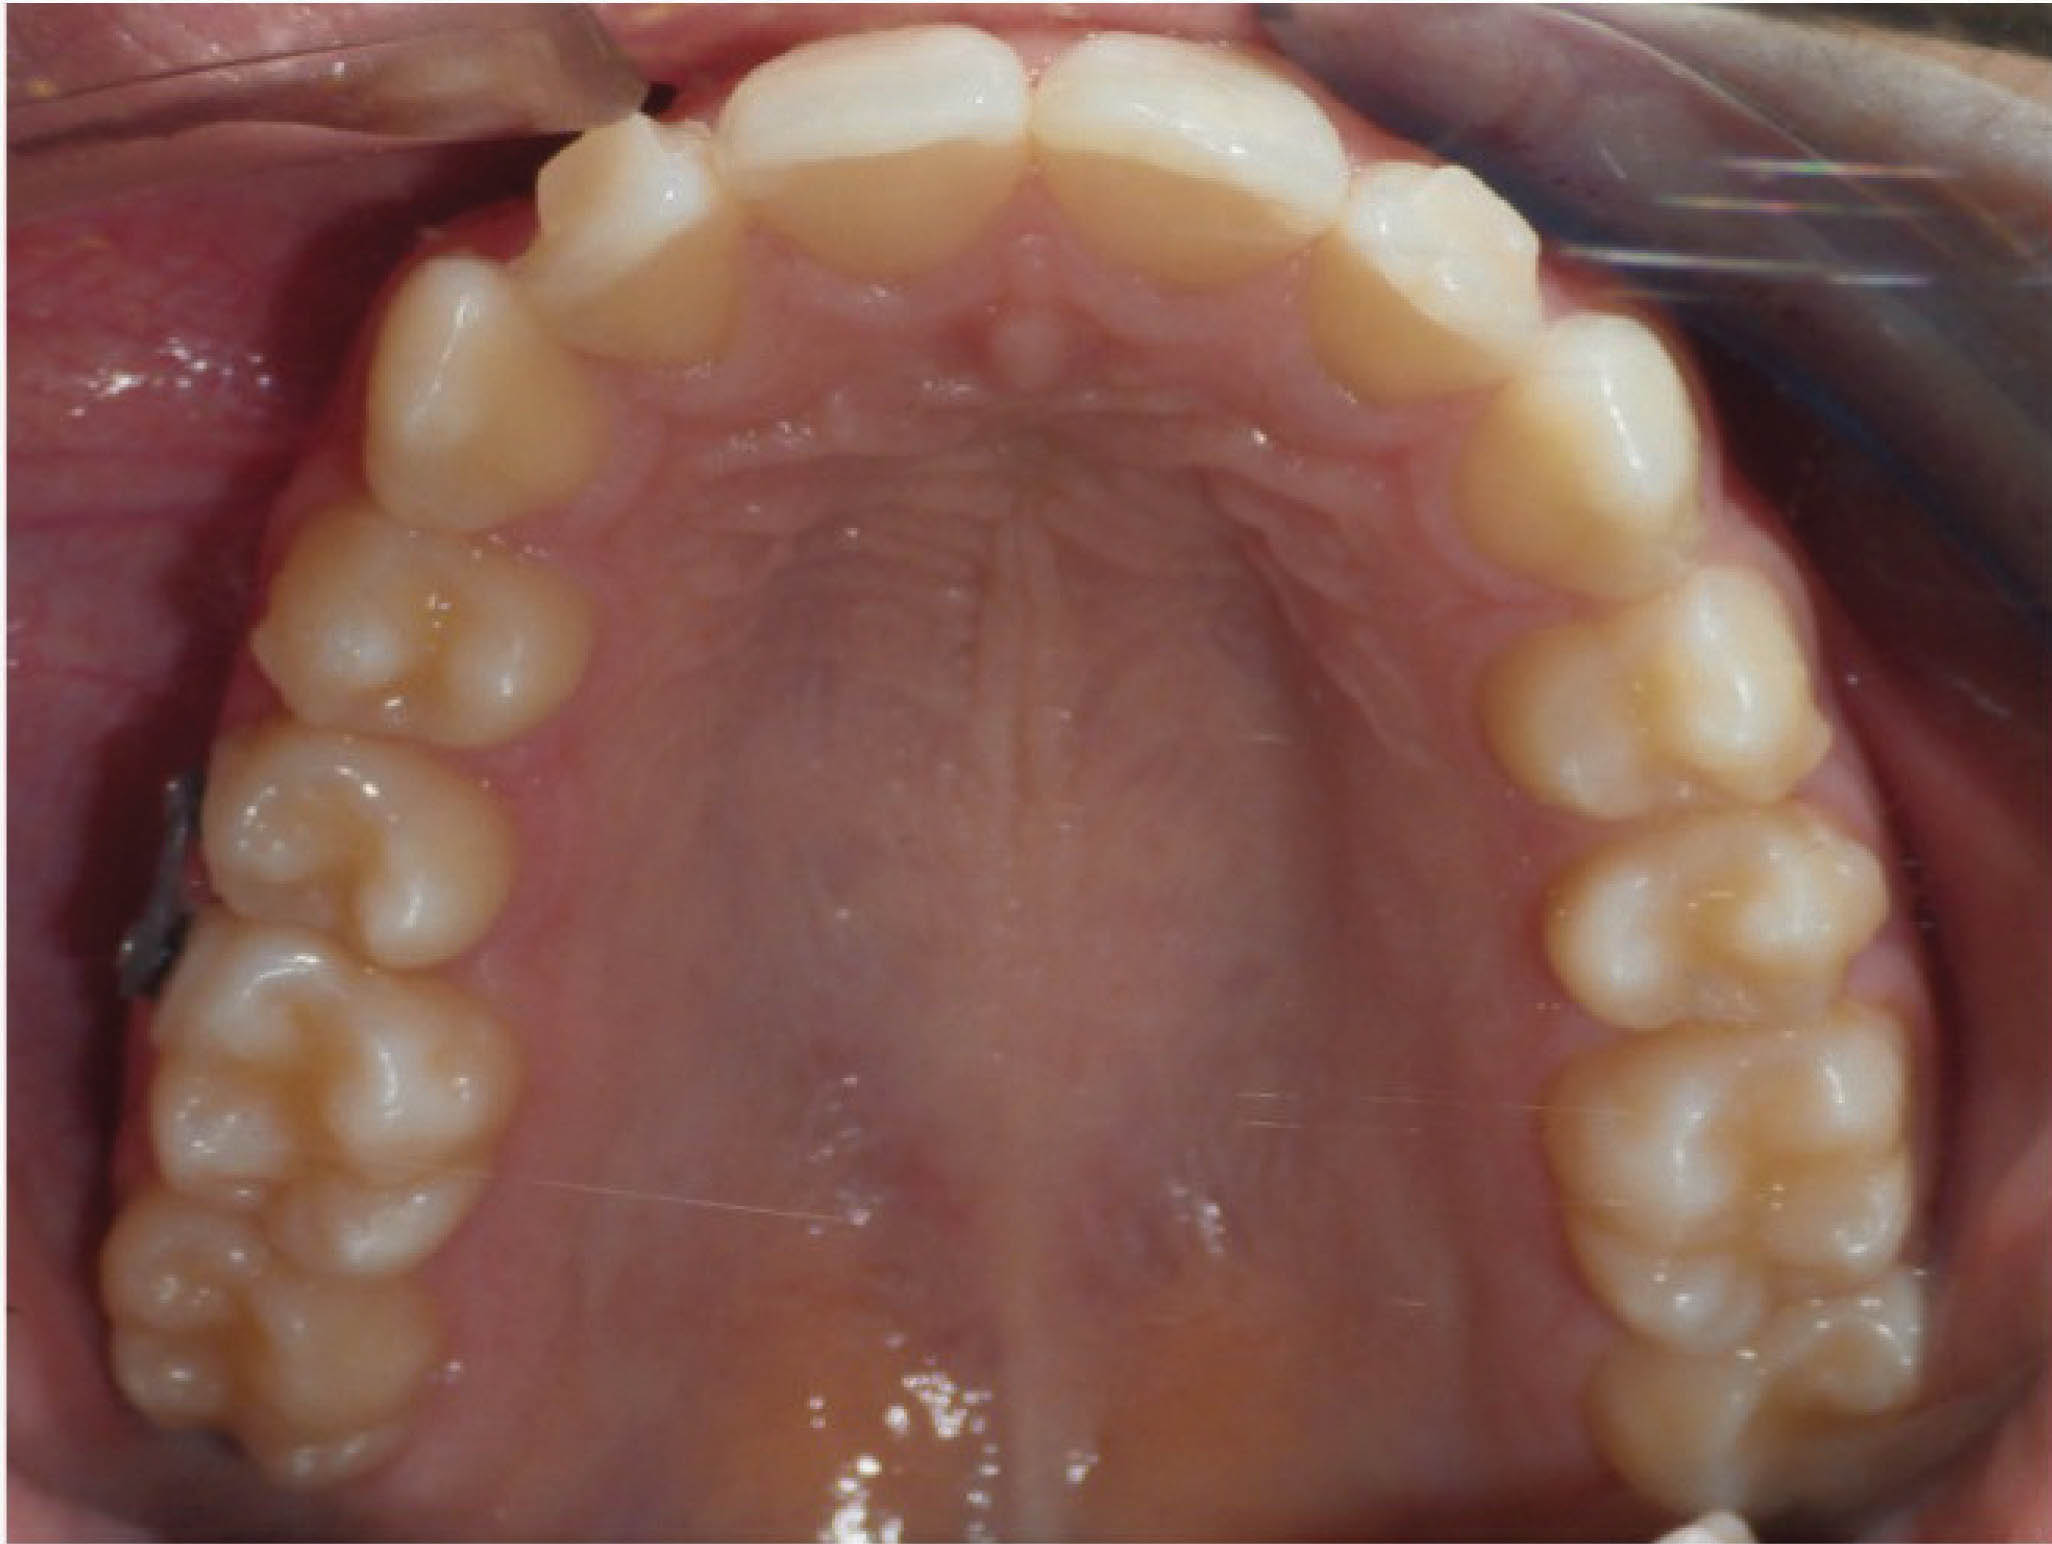

قانون کلی برای تورک ۳۰-۱۰ درجه درمان اضافه است که متناسب با بیمار شما تعیین میشود. در بیمار 167-6 باید لترالهای بالا را از کراس خارج کنیم. درمان چه با ارتو ثابت چه با الاینرها در سمت تاج رخ میدهد، لذا لترالها همیشه به سمت لبیال تیپ میشوند که میلی به این حالت نداریم. میخواهیم که این دندانها بادیلی حرکت کنند. برای این بیمار ۳۰ درجه حرکت بیشتر لبیالی ریشه لترالهای بالا در نظر گرفته شد.

شکل 167-6

تصویر 168-6 ماه ۲۲ را نشان میدهد، و میبینید که جایگاه لترال چپ بالا خوب است و ریشه هم وضعیت خوبی دارد. تورک اضافه باکالی ریشه ۳۰ درجه که به ریشه لترال بالا دادیم در دهان وجود ندارد. در واقع این میزان تورک برای جلوگیری از تیپ شدن لبیالی تاج و رسیدن به زاویه صحیح ریشه است.

شکل 168-6